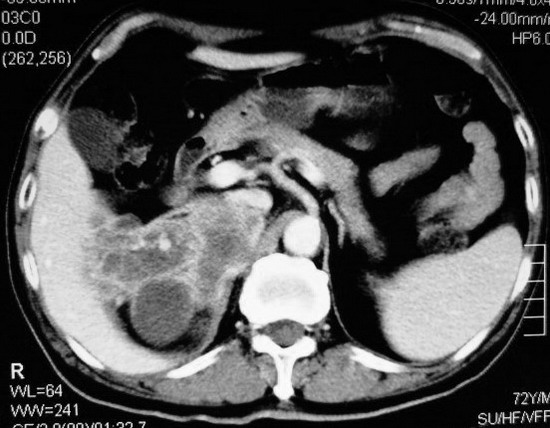

以下是引用杀毒软件在2008-11-17 19:15:00的发言:[br]考虑------右肾癌合并肾静脉---同侧肾上腺受侵可能性大

以下是引用zjzjr在2008-11-17 20:45:00的发言:[br]考虑------右肾癌合并肾静脉---同侧肾上腺受侵可能性大及腹膜后淋巴结转移.